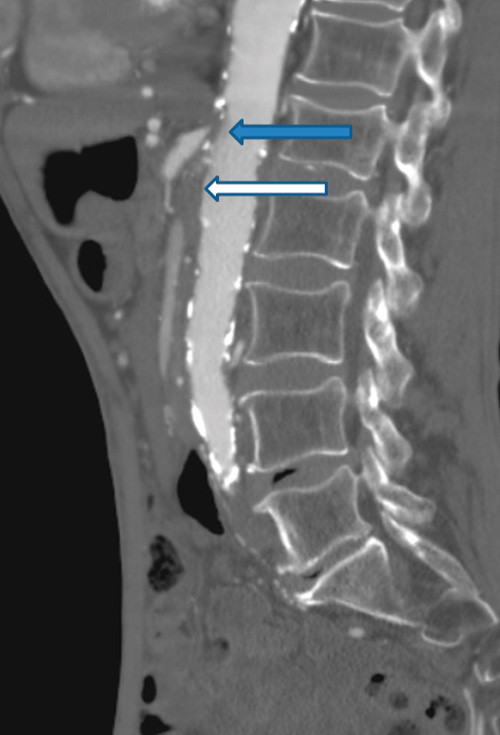

Man gransket på nytt CT abdomen utført for tre år siden. Undersøkelsen var gjort med intravenøs kontrast på mistanke om kronisk pankreatitt som årsak til magesmertene. Det ble ikke funnet tegn til pankreatittforandringer, men det ble bemerket uttalte arteriosklerotiske forandringer i abdominalaorta, proksimale bekkenkar, arteria mesenterica superior og truncus celiacus. De beskrevne forandringene i abdominalkarene ble den gang ikke fulgt videre opp. På bakgrunn av CT- funnet fra tre år tidligere valgte man nå å utføre abdominal CT- angiografi. Undersøkelsen viste en 2,5 cm lang okklusjon av a. mesenterica superior og en 8 mm lang okklusjon av truncus celiacus, begge okkludert fra avgangen fra lumbalaorta. A. mesenterica inferior var åpen, men med sannsynlig signifikant avgangsstenose, dvs. 75 % eller større reduksjon av karets tverrsnittsareal (fig 3).

Tykk- og tynntarm forsynes hovedsakelig av a. mesenterica superior og a. mesenterica inferior. Til duodenum bidrar også kar fra truncus celiacus (2). Flere tilstander kan gi iskemisk kolitt, men spesifikk årsak kan være vanskelig å finne. Hos vår pasient var arteriosklerose mest sannsynlige årsak. Vår pasient var storrøyker, hadde distal klaudikasjon med påviste arteriosklerotiske forandringer i perifere kar i underekstremitetene, hypertensjon og diabetes mellitus. Man mistenkte derfor nedsatt blodforsyning til tarm som årsak til hans plager.